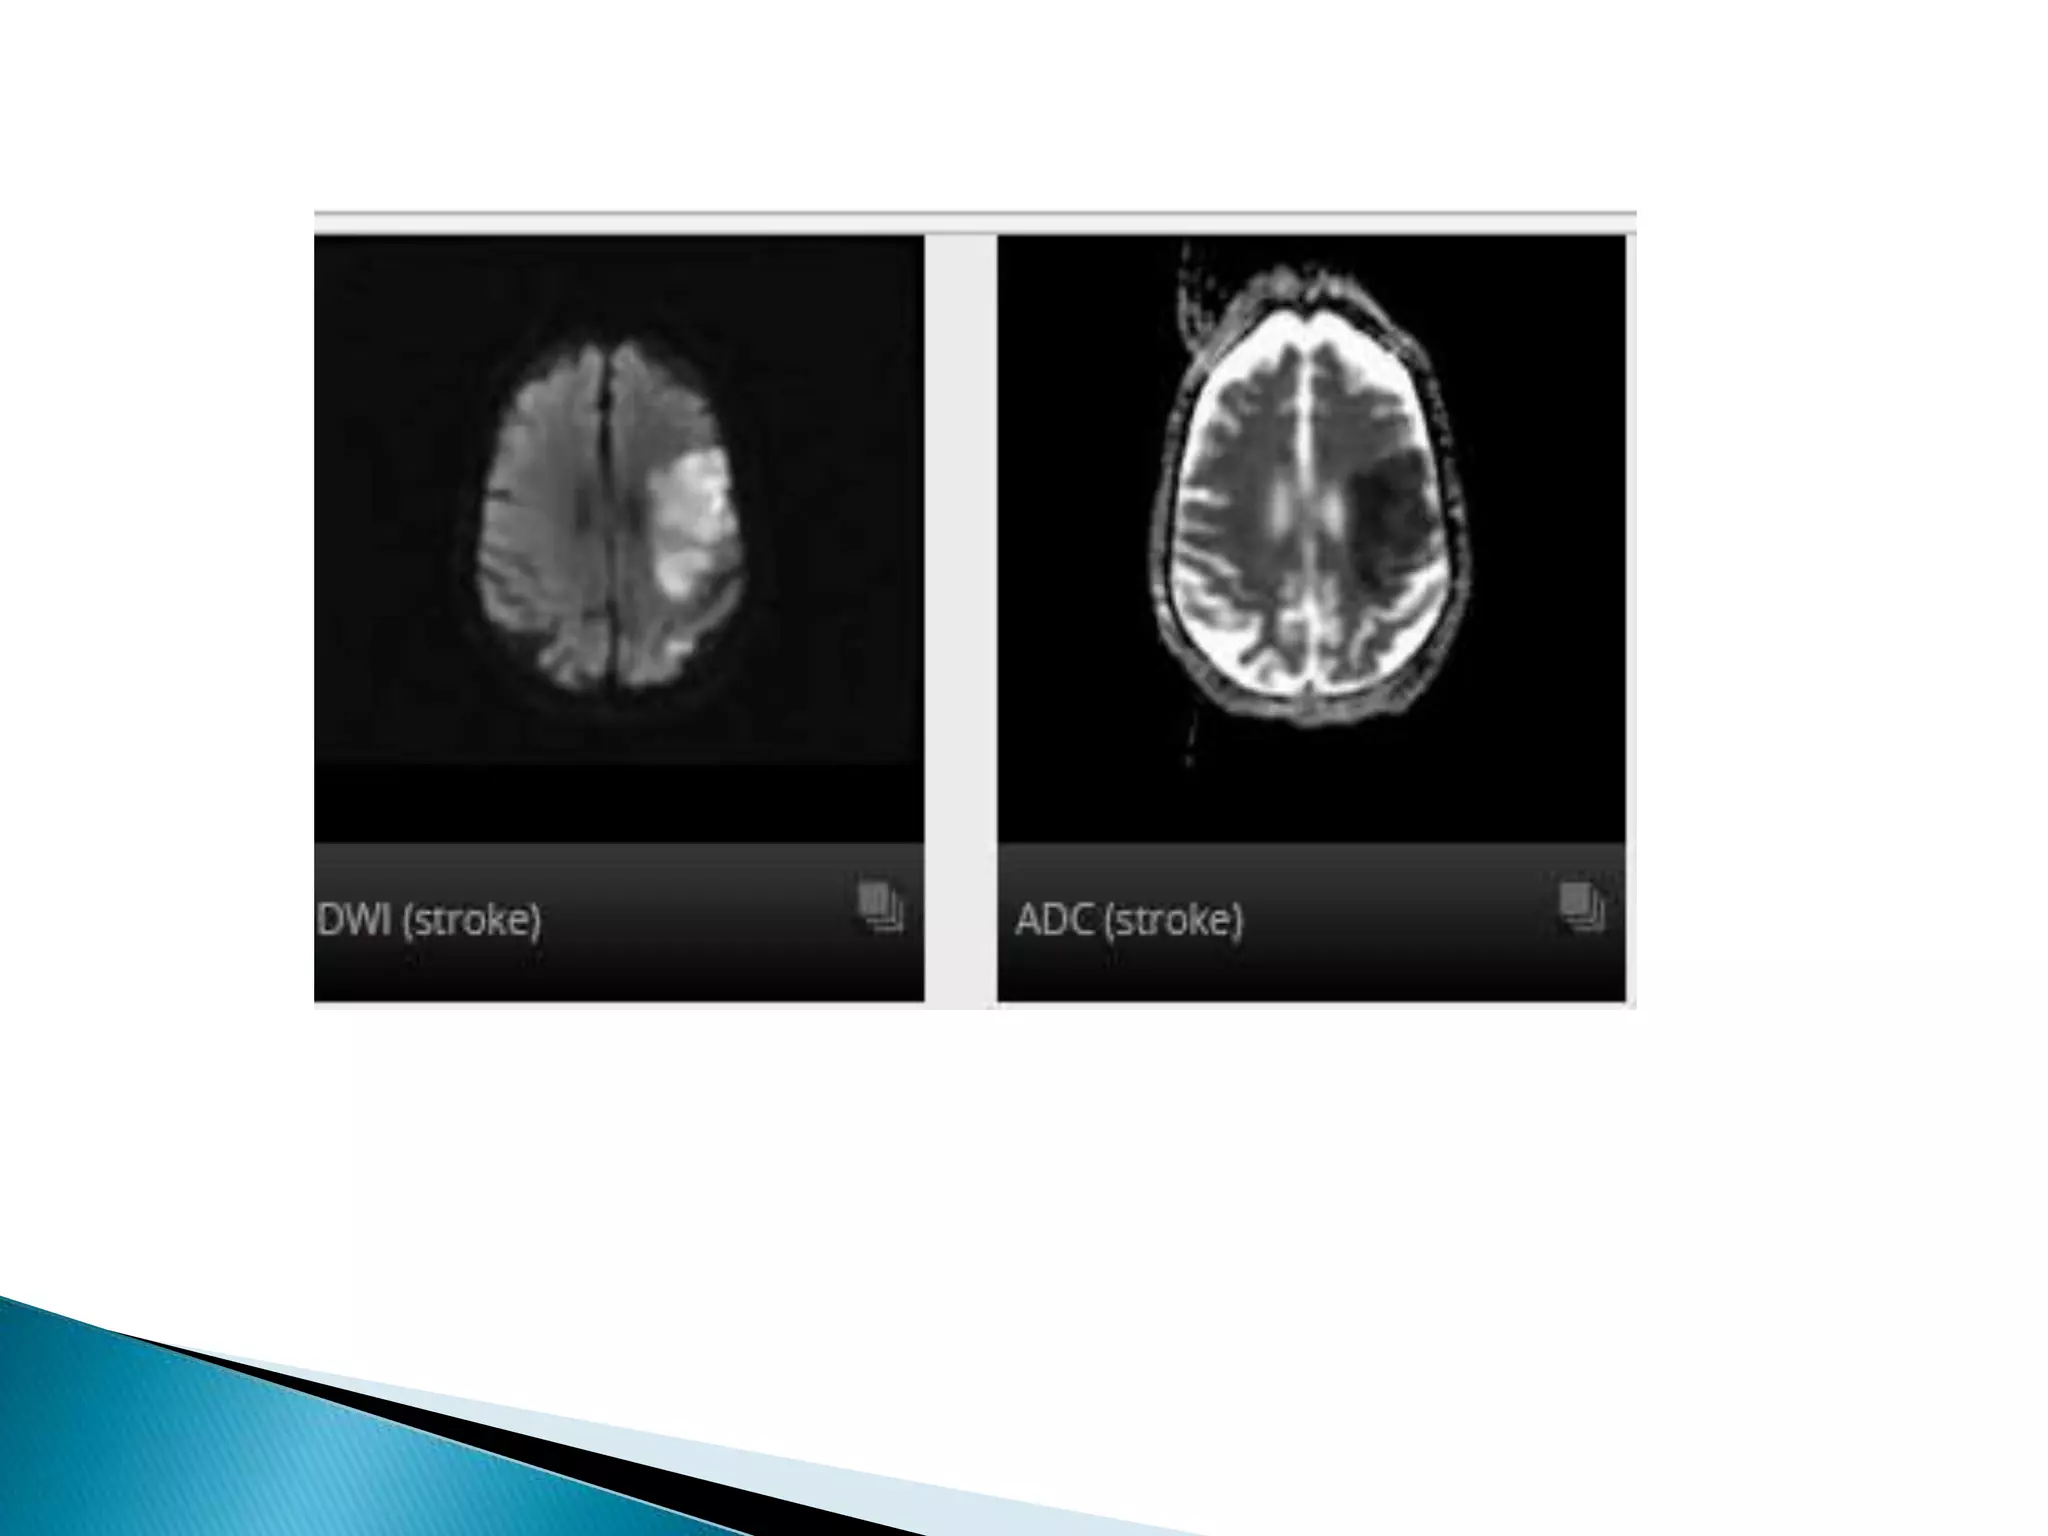

This document lists various medical conditions and provides brief descriptions: A) Abscess, B) Brain infarction and hypoxic insult, C) Crutzfield Jacob disease, D) Diffuse axonal injury and demyelination, E) Encephalitis caused by HSV virus and epidermoid cyst. It also mentions imaging sequences and differential diagnoses for conditions like ischemic stroke and limbic encephalitis.